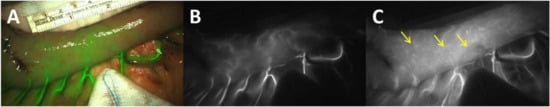

Figure 5.

Fluorescence image of the gastric tube during surgery with the overlay image (A), the near infrared image at the influx timepoint of ICG (τ), clearly depicting the arteries (B). After influx in the arteries, perfusion of the microvascular network (yellow arrows) is visible in the NIR image (C) τ + 10 s. The sterile gauze indicates the watershed. Upper scale of the metric ruler is in cm.